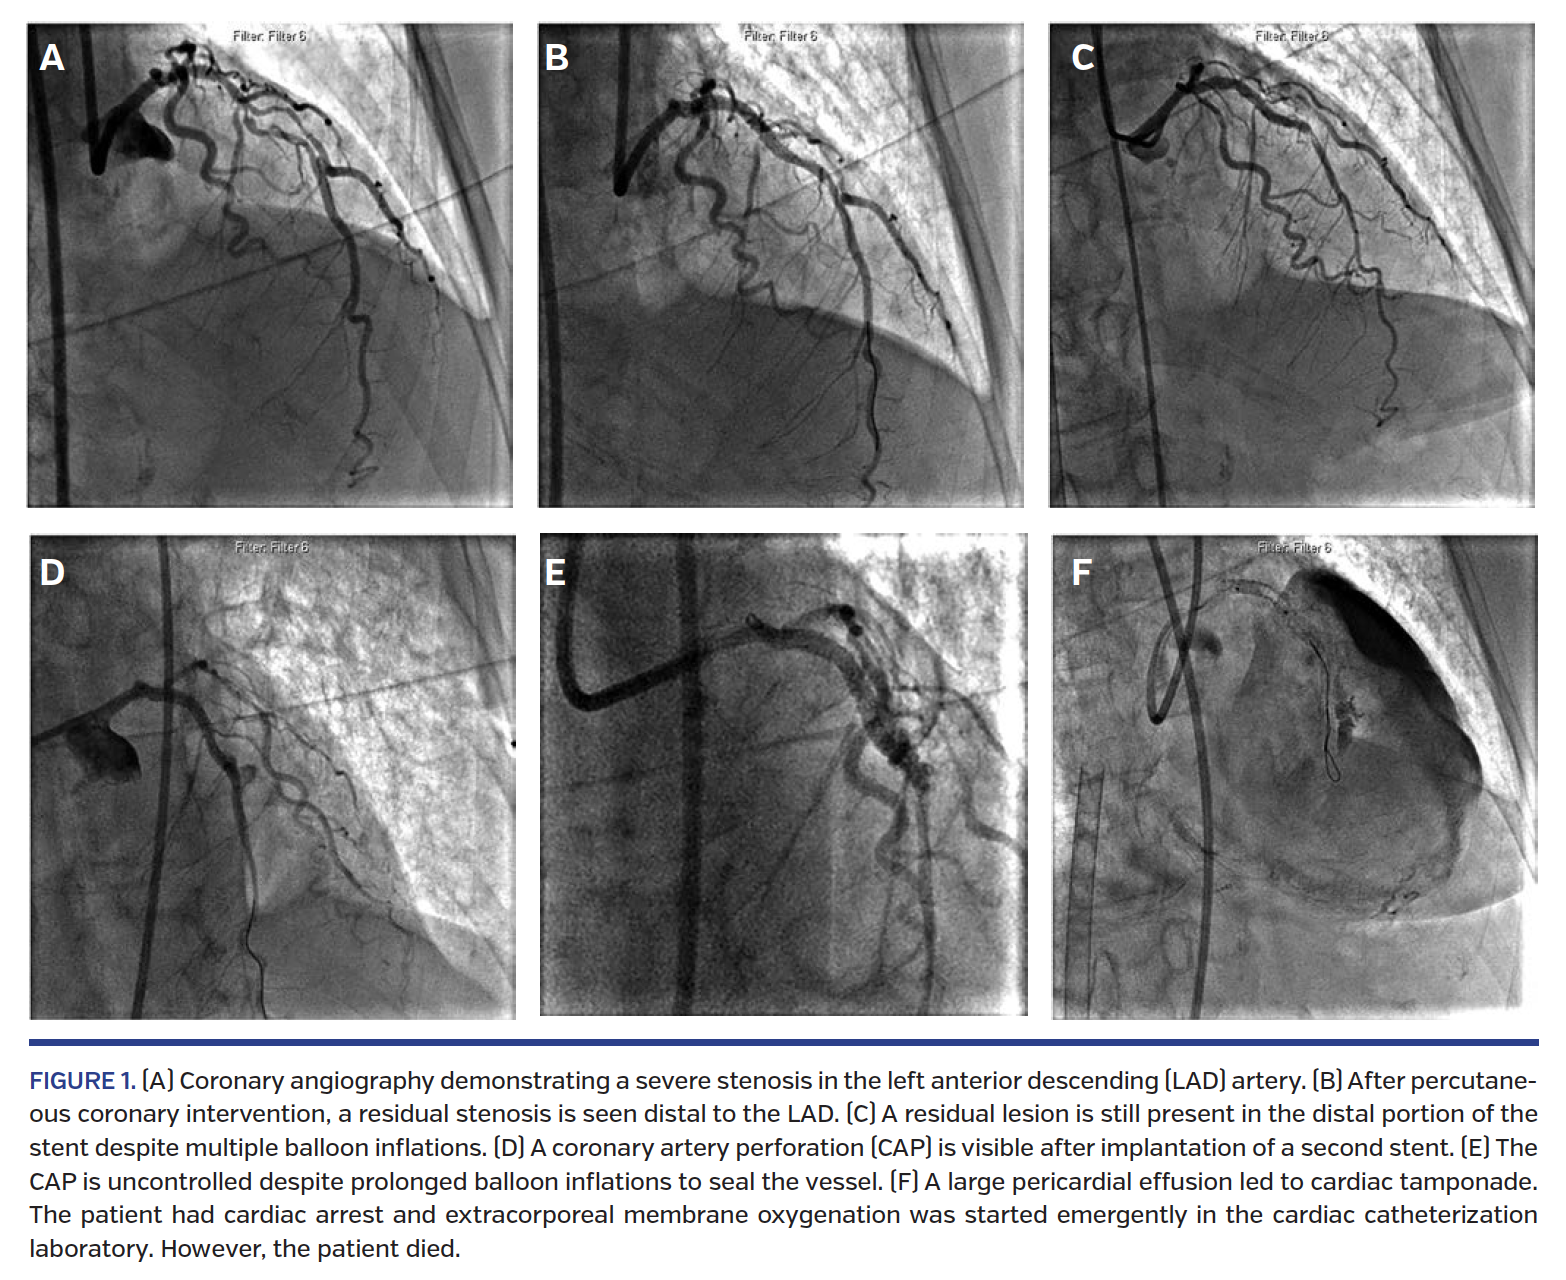

Balloon oversizing. Larger balloon-to-artery ratio was associated with CAP (1.3 ± 0.3 vs 1.0 ± 0.3; P<.001) (Figure 1).15 In 62 patients with CAP, of those who underwent balloon angioplasty, the device-to-artery ratio was higher in patients who had CAP compared with those who did not have CAP (1.19 ± 0.17 vs 0.92 ± 0.16; P=.03).5 Another study reported that higher balloon-to-artery ratio was associated with CAP (odds ratio [OR], 7.62; 95% confidence interval [CI], 2.78-20.77; P=.01).10 The use of compliant balloons was a predictor of emergency CABG and/or in-hospital death (OR, 4.32; 95% CI, 1.60-11.65; P=.01).10 In addition, high-pressure inflation of resistant lesions may also increase the risk of CAP.

Perforation classification and complications. Given that the majority of studies utilize the Ellis classification of CAP, the following discussion also uses that scheme. Ellis type I CAP is generally considered a benign condition that does not often lead to tamponade or death.5,16 Ellis type II CAP is also usually benign, but there are higher rates of tamponade, emergency CABG, and death (Table 3).16 Ellis type III CAP is usually clinically more severe, with respect to need for urgent pericardiocentesis, intraaortic balloon pump insertion, emergent cardiac surgery, and mortality as compared with type I and II CAP.11,12,16,31 When compared with type I CAP, types II and III CAP had higher rates of in-hospital death (21.9% vs 2.7%; P=.02), tamponade (37.5% vs 2.7%; P<.001), and composite endpoint of in-hospital death, cardiac tamponade, or emergent cardiac surgery (46.9% vs 5.6%; P<.001).32 Fortunately, type III CAP is rare, with an incidence of 0.23%.33 Consequences of type III CAP are severe, however, with mortality of 7%-44%, tamponade up to 40%, and 20%-40% need for emergent CABG.11,16,33,34 Lesion complexity is a critical risk factor for developing type III CAP. Of 56 patients with type III CAP, 96% of lesions were ACC/AHA type B2 or type C and 28.6% were chronic total occlusions.33

Cardiac tamponade. CAP can lead to bleeding into the pericardium, resulting in cardiac tamponade and possibly hemodynamic collapse. The incidence of CAP that progress to tamponade ranges from 10%-60%.4 Important factors that influence that range include type of CAP, type of anticoagulation, and rate of blood accumulation. Cardiac tamponade is associated with complex lesions, mainly type B2 and C lesions,36,37 and type III CAP1,3,5,13 as well as atheroablative devices.36,38

Early recognition and treatment are crucial for survival after CAP. The goal of CAP management is to seal the site of extravasation and to treat hemodynamic instability from pericardial effusion or tamponade. Although there have been proposed algorithms for CAP management,3,7,14,32,33 there is no consensus on optimal treatment of CAP and protocols may vary by institution (Figures 4 and 5). Several factors impact the management of CAP, including CAP grade, presence/duration of pericardial effusion or tamponade, and hemodynamic status.

Prolonged balloon inflation. Low-pressure balloon inflation may help seal the CAP while allowing distal vessel perfusion to prevent ischemia. Ellis type I and II CAP have been successfully managed with prolonged balloon inflation.10,31 In a retrospective study of 30 CAP cases, 29 were treated with balloon inflation.31 All patients with type I and II CAP were successfully treated with prolonged balloon inflation with or without pericardiocentesis, while only 64% of type III CAP were successfully treated. Of the patients with type I and II CAP, 84% were managed by balloon inflation alone. There was a numerically higher incidence of tamponade and pericardiocentesis with type III CAP compared with type I/II CAP that were treated with balloon inflation (11% vs 27%). Balloon inflation time was significantly longer in cases of stent-related CAP compared with cases of wire/balloon-related CAP (44 ± 37 minutes vs 21 ± 13 minutes, respectively; P<.05). Duration was also significantly longer in type III CAP compared with type I/II CAP (48 ± 37 minutes vs 20 ± 13 minutes; P<.05).31